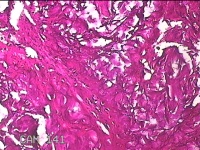

左肘关节肿物(痛风石)

发现左肘关节肿物2年余。

灰白暗红色组织5.5x4x2.3cm一块,表面带梭形皮肤5.5x3.3cm,皮下见肿物5.5x2x1.3cm一个,切开肿物,内见大量石灰样物,内壁粗糙。